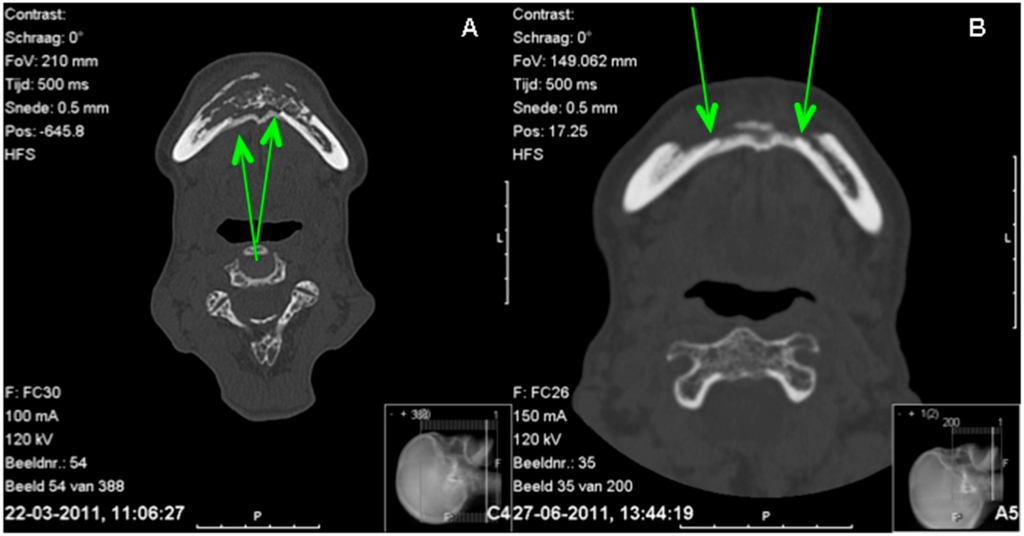

Figure 3.

Comparison CT scans before (A) and three months after surgery (B). A = lingual subperiosteal bone can be seen and seems to connect both parts of the mandible; B = the difference between the cortex of the mandible and the subperiosteal bone is decreasing.

The pre- and post-operative CT scan confirmed this finding: that the continuity of the original lingual cortex of the region from 34 to 45 was gone and replaced by subperiosteal bone (Figure 3B).

The CT scan also showed that the subperiostal bone developed a cortex-like structure (Figure 3B). The distinction between the former cortex of the mandible and the cortex of the neo-mandible was visible on the CT scan (Figure 3B). Where the first CT scan made at presentation clearly shows a distinction between the subperiosteal bone and the lingual cortex, the second CT scan made several weeks after presentation appears to have no such clear distinction anymore. It seems as if a new cortex has been formed.

The patient’s recovery was good without further complaints, intraoral dehiscences or fistulas (Figure 1C). During follow-up, no pathological fracture of the subperiosteal bone occurred. The panoramic radiograph showed continuity of the mandible and a cortex-like structure. The CT scan six weeks after surgery showed a lingual neo-cortex of the mandible without any signs of resorption (Figure 3B). At follow-up after nine months, the patient was still free of complaints.